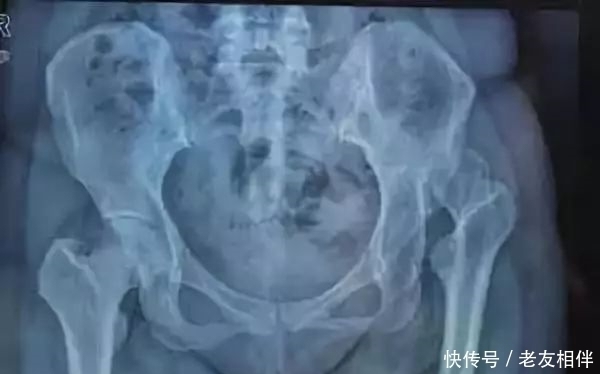

3、骨折

骨折是由于意外事故、跌倒或运动受伤而导致的身体上的骨折。其他原因可能是由于老年人骨质疏松症或者骨密度低下。这两者都导致骨质疏松。

髋部骨折包括股骨骨干骨折和骨盆骨折,老年人常见股骨颈骨折,致死率很高!

这些损伤后需要立即就医,骨头可以通过石膏模型、夹板或外科手术重新组合,手术使用钢板或螺钉固定骨折,从而使骨头愈合并重新长在一起。